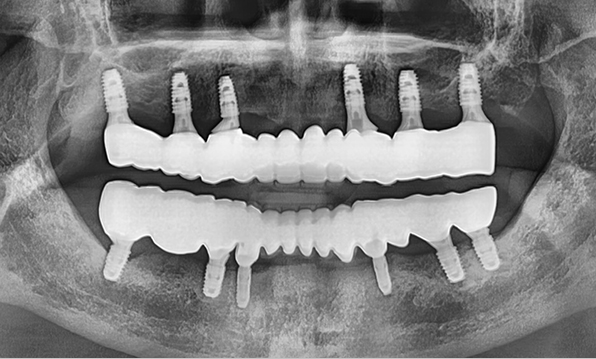

Using a method of placing 8–9 implants in the maxilla and 8 implants in the mandible, this approach fully restores all 28 natural teeth, creating an oral environment most closely resembling

natural dentition.

Using a method of placing 6–7 implants in the maxilla and 6 in the mandible, this approach restores both posterior and anterior teeth, efficiently rehabilitating the entire oral cavity.

Case 02

Before After